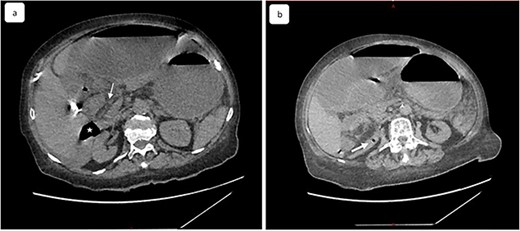

Our patient underwent an emergency laparotomy and the internal hernia was reduced manually after coloepiploic detachment. The herniated ileum and colon was found to be ischemic and was subsequently resected (Fig. 4) and a right double ileo-colostomy was performed. The histology of right colectomy showed lesions of acute ischemic colitis with hemorrhagic infarction of the ileocecal resection and appendix and no signs of malignancy were observed. The patient recovered well postoperatively with normalization of blood biology within several days. The stoma was viable and productive. She was discharged from the surgery department 10 days later and was referred to the medical department for the treatment of mixed connective tissue disease (MCTD) and died 2 months later from a severe pneumonia.

Image showing the incarcerated ileum and coecum after large surgical resection.